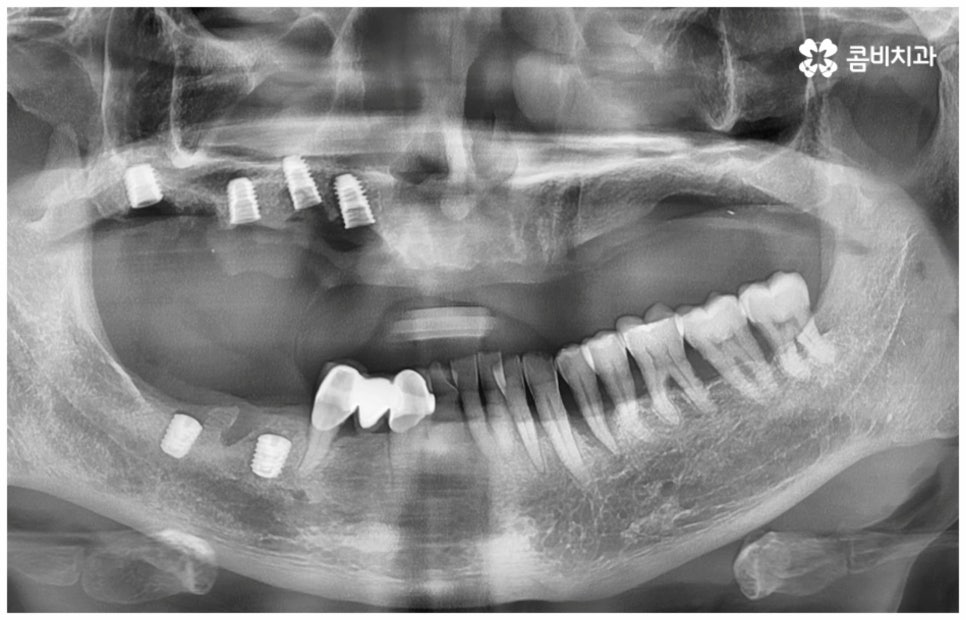

그러나 노화나 구강 질환을 원인으로 한 경우에는 식립 절차가 좀 더 복잡해 질 수 있는데요. 잇몸병을 예로 들어 생각해 보면 자연스러운 노화 및 관리 소홀로 인해 치아 주변 조직 (잇몸, 치주인대, 치조골 등) 에 염증 반응이 생기는 병인 치주 질환이 많이 심해졌을 때 상황에 따라 해당 자연 치아를 살리지 못하고 발치를 해야할 수도 있는 거예요. 이렇게 치주질환을 이유로 임플란트 식립을 진행할 때에는 식립 성공률을 높이고 임플란트수명 을 늘리기 위해 먼저 치주질환 치료를 선행해 줘야 하며, 환자분들의 상황에 따라 뼈이식 또는 상악동 거상술을 통해 잇몸뼈를 보충해 줘야 할 수도 있어요. 치조골이 이미 많이 녹아 있거나 병증이 극심하다면 임플란트 식립 난이도가 매우 높아지거나 때로는 불가능해 질 수 있기 때문에 다양한 임상 경험을 통해 풍부한 노하우를 가지고 있는 의료진에게 진단 및 치료를 받는 것이 굉장히 중요한 포인트라고 할 수 있습니다.

보통 정확한 위치에 식립하고 철저하게 사후 관리를 해 준다면 임플란트수명 은 거의 반영구적이라고 할 정도로 오랫동안 건강하게 사용할 수 있습니다. 그러기 위해서는 처음 식립할 때 환자분들의 상황에 맞게 체계적인 계획을 세워 정밀한 식립을 진행할 수 있는 시술자의 높은 숙련도 외에도 꼼꼼한 검사를 위한 3D-CT 와 같은 정밀 진단 장비를 갖추고 있는지 여부를 살펴보실 필요가 있어요. 이를 통해 환자분들 각각의 구강 구조, 치조골 상태 (밀도나 두께 등), 신경이나 혈관과 같은 주변 조직 등을 정확하게 분석한 다음 오랜 임상데이터를 바탕으로 높은 성공률을 보이고 있는 정품 재료를 사용하여 식립을 진행하는 것이 임플란트수명 을 늘리는데 도움을 주므로 이런 점들 역시 신경써서 살펴보시길 권유드리고 있습니다.